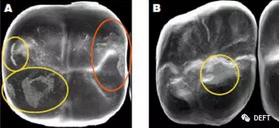

有學(xué)者的研究證實(shí):釉面會(huì)被迅速磨耗而且變得粗糙,反而會(huì)磨耗對(duì)頜牙。(圖3)

360截圖20170125143623545.jpg

圖3  A圖:顯示了對(duì)頜牙在BruxZir全鋯冠上造成的磨損的平面,黃色圓圈代表復(fù)合樹(shù)脂和釉質(zhì),橙色圓圈代表瓷。B圖:顯示了對(duì)頜牙為鑄造金屬修復(fù)體時(shí),對(duì)切削類e.maxCAD單冠造成的磨損平面。兩種牙冠表面都有小的磨損平面,而且他們的對(duì)頜牙都顯示出了良好的結(jié)果。臨床上,對(duì)頜牙的每種材料(瓷、樹(shù)脂、釉質(zhì)、鑄造金屬)被磨損的程度幾乎是等同的。